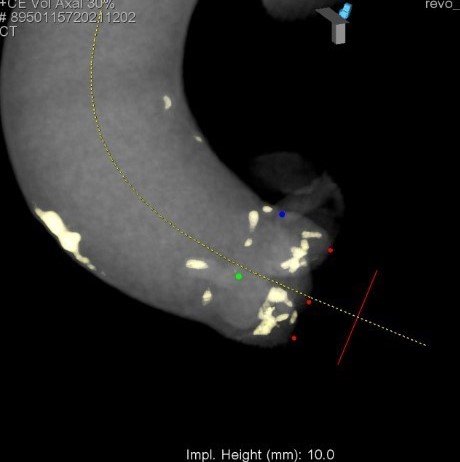

大動脈弁計測画像

腹部大動脈瘤術前CT

大動脈弁狭窄症(BAV施行時の大動脈造影)

TAVI術後造影